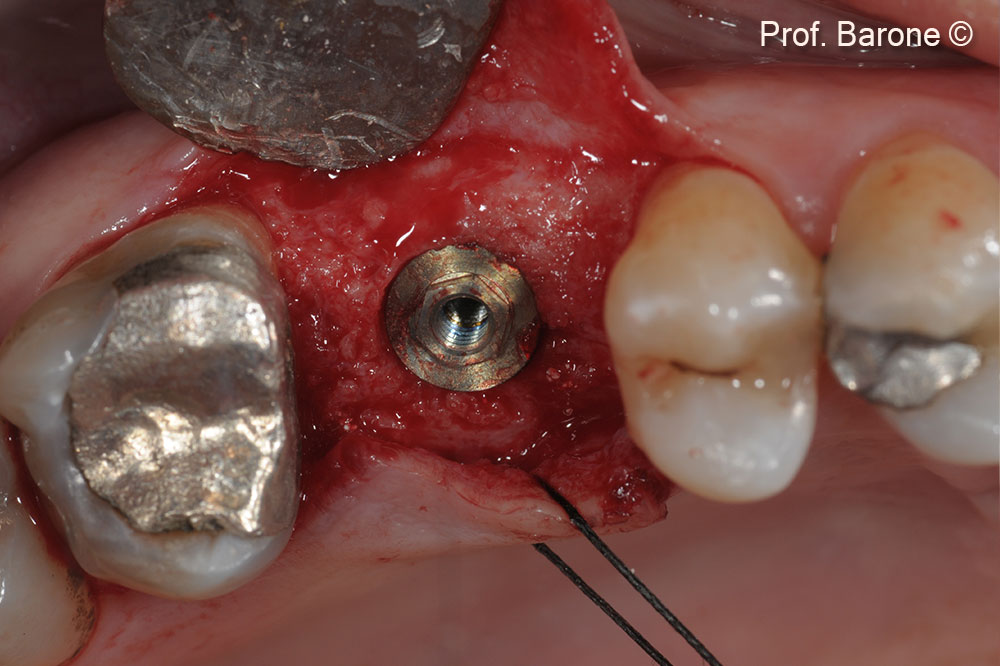

Implant Placement after 5 months